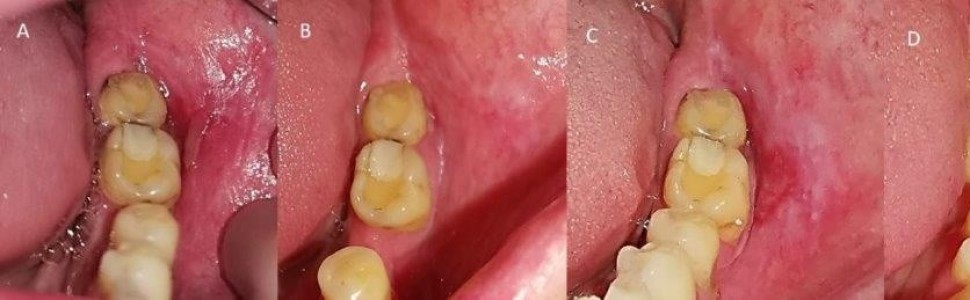

Liszaj płaski jest przewlekłym schorzeniem śluzówkowo-skórnym o podłożu autoimmunologicznym, przebiegającym z okresami zaostrzeń i remisji. Może ono przybierać różne postaci kliniczne – od łagodnych, zwykle bezobjawowych form (postacie białe), aż po ciężkie atroficzne, nadżerkowe i pęcherzowe zmiany (postacie czerwone). Etiologia choroby nie została do końca poznana, jednak wpływ na jej ujawnienie się mogą mieć czynniki genetyczne, psychogenne (stres), infekcyjne, stosowanie niektórych leków (np. przeciwcukrzycowych, przeciwnadciśnieniowych), a także materiały stomatologiczne. Konwencjonalne leczenie objawowych postaci liszaja płaskiego jamy ustnej preparatami steroidowymi oraz lekami immunosupresyjnymi jest zazwyczaj skuteczne, jednak obarczone pewnym ryzykiem działań niepożądanych. Celem niniejszej pracy była prezentacja przypadków leczenia objawowych postaci liszaja płaskiego jamy ustnej u dwóch pacjentów: 52-letniego mężczyzny (pacjent 1) oraz 77-letniej kobiety (pacjent 2). U obydwu osób zastosowano klasyczną miejscową terapię steroidową za pomocą żelu z 0,025% fluocynolonem w schemacie: 2 tygodnie steroidu – 2 tygodnie przerwy – 2 tygodnie steroidu. Na wizycie kontrolnej po tygodniu od zakończenia leczenia stwierdzono całkowite wygojenie zmian na błonie śluzowej i ustąpienie dolegliwości bólowych u obydwu pacjentów. Z kolei po miesiącu tylko u pacjenta 2 utrzymywała się remisja, podczas gdy u pacjenta 1 zaobserwowano wznowę, przy czym objawy kliniczne i subiektywne były łagodniejsze niż przed leczeniem.

Lichen planus is a chronic mucocutaneous autoimmune disease which progresses with periods of exacerbations and remissions. It can range in clinical form from mild, usually asymptomatic forms (white forms) to severe erosive, atrophic and bullous lesions (red forms). The etiology of the disease is not fully understood, but genetic, psychogenic (stress) and infectious factors, as well as certain medications (e.g., those used to treat hypertension, diabetes) or dental materials may have an impact on its manifestation. Conventional treatment of symptomatic types of oral lichen planus based on corticosteroids and immunosuppres sant drugs is usually effective, however, it carries the risk of side effects. The aim of this report was to present the treatment of symptomatic forms of oral lichen planus in two patients: a 52-year-old man and a 77-year old woman. Both patients were treated with topical steroid therapy with 0.025% fluocynolone gel in the scheme: 2 weeks of steroid – 2 weeks off – 2 weeks of steroid. At the follow-up visit one week after the end of treatment, complete healing of the mucosal lesions and total relief of pain were observed in both patients. In contrast, after a period of one month, only patient 2 remained in remission, while patient 1 showed recurrence, with clinical and subjective symptoms milder than before treatment.